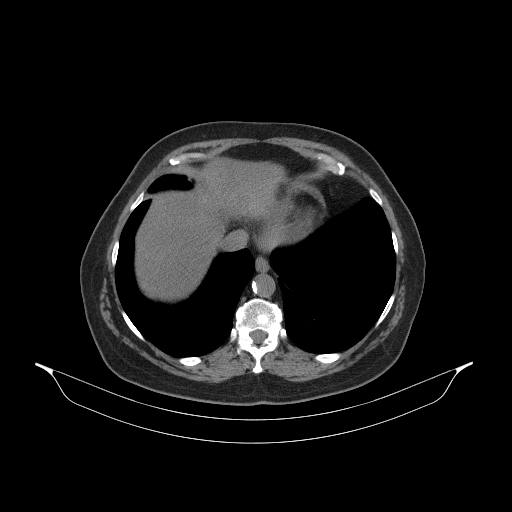

Generated VENOUS CT scan (A→B translation)

Full window (WL 1023.5, WW 4095 β†’ Low βˆ’1024, High +3071)

Actual HU range: [-1024.0, 1197.0]

Lung window (WL -600, WW 1500 β†’ Low βˆ’1350, High +150)

Actual HU range: [-1350.0, 150.0]

Mediastinum window (WL 40, WW 400 β†’ Low βˆ’160, High +240)

Actual HU range: [-160.0, 240.0]